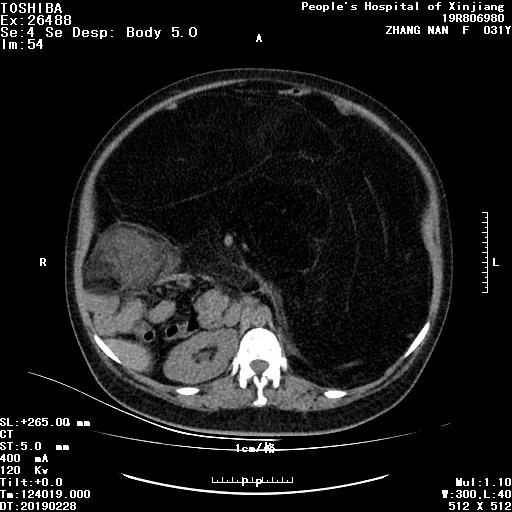

8 年前,她体重 63 kg,身高 163 cm,妊娠后体重进行性增加约 36 kg,可是产后,她的体重最重竟达 91 kg。 本来以为自己只是长胖了,...